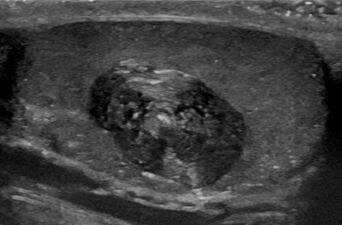

كيس بشري في الخصية بالموجات فوق الصوتية ، مع مظهر مصفح ("قشرة البصلة").